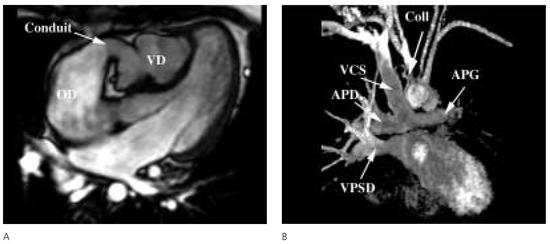

Collatérales Veineuses Systémiques Après Dérivation Cavo-Pulmonaire Totale

by Pedro Trigo Trindade, Dominique Didier, Beat Friedli, Maurice Beghetti and Yacine Aggoun

Cardiovasc. Med. 2005, 8(5), 207; https://doi.org/10.4414/cvm.2005.01101 - 27 May 2005

Viewed by 102

Abstract

Une patiente de 18 ans, élève-infirmière, connue pour une cardiopathie congénitale [...] Full article

Show Figures

Figure 1